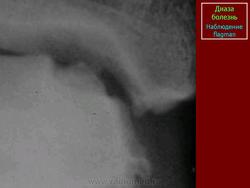

Диаза болезнь (m. Dias), рассекающий остеохондроз тела таранной кости, остеохондрит таранной кости.

Наблюдается у детей в возрасте 6-12 лет в виде асептического некроза блока таранной кости. Отмечается боль, припухлость в области голеностопного сустава. На рентгенограмме выявляется участок уплотнения костной ткани, иногда ограниченный узкой зоной просветления. В редких случаях некротизированный костный фрагмент отделяется и выпадает в полость голеностопного сустава.